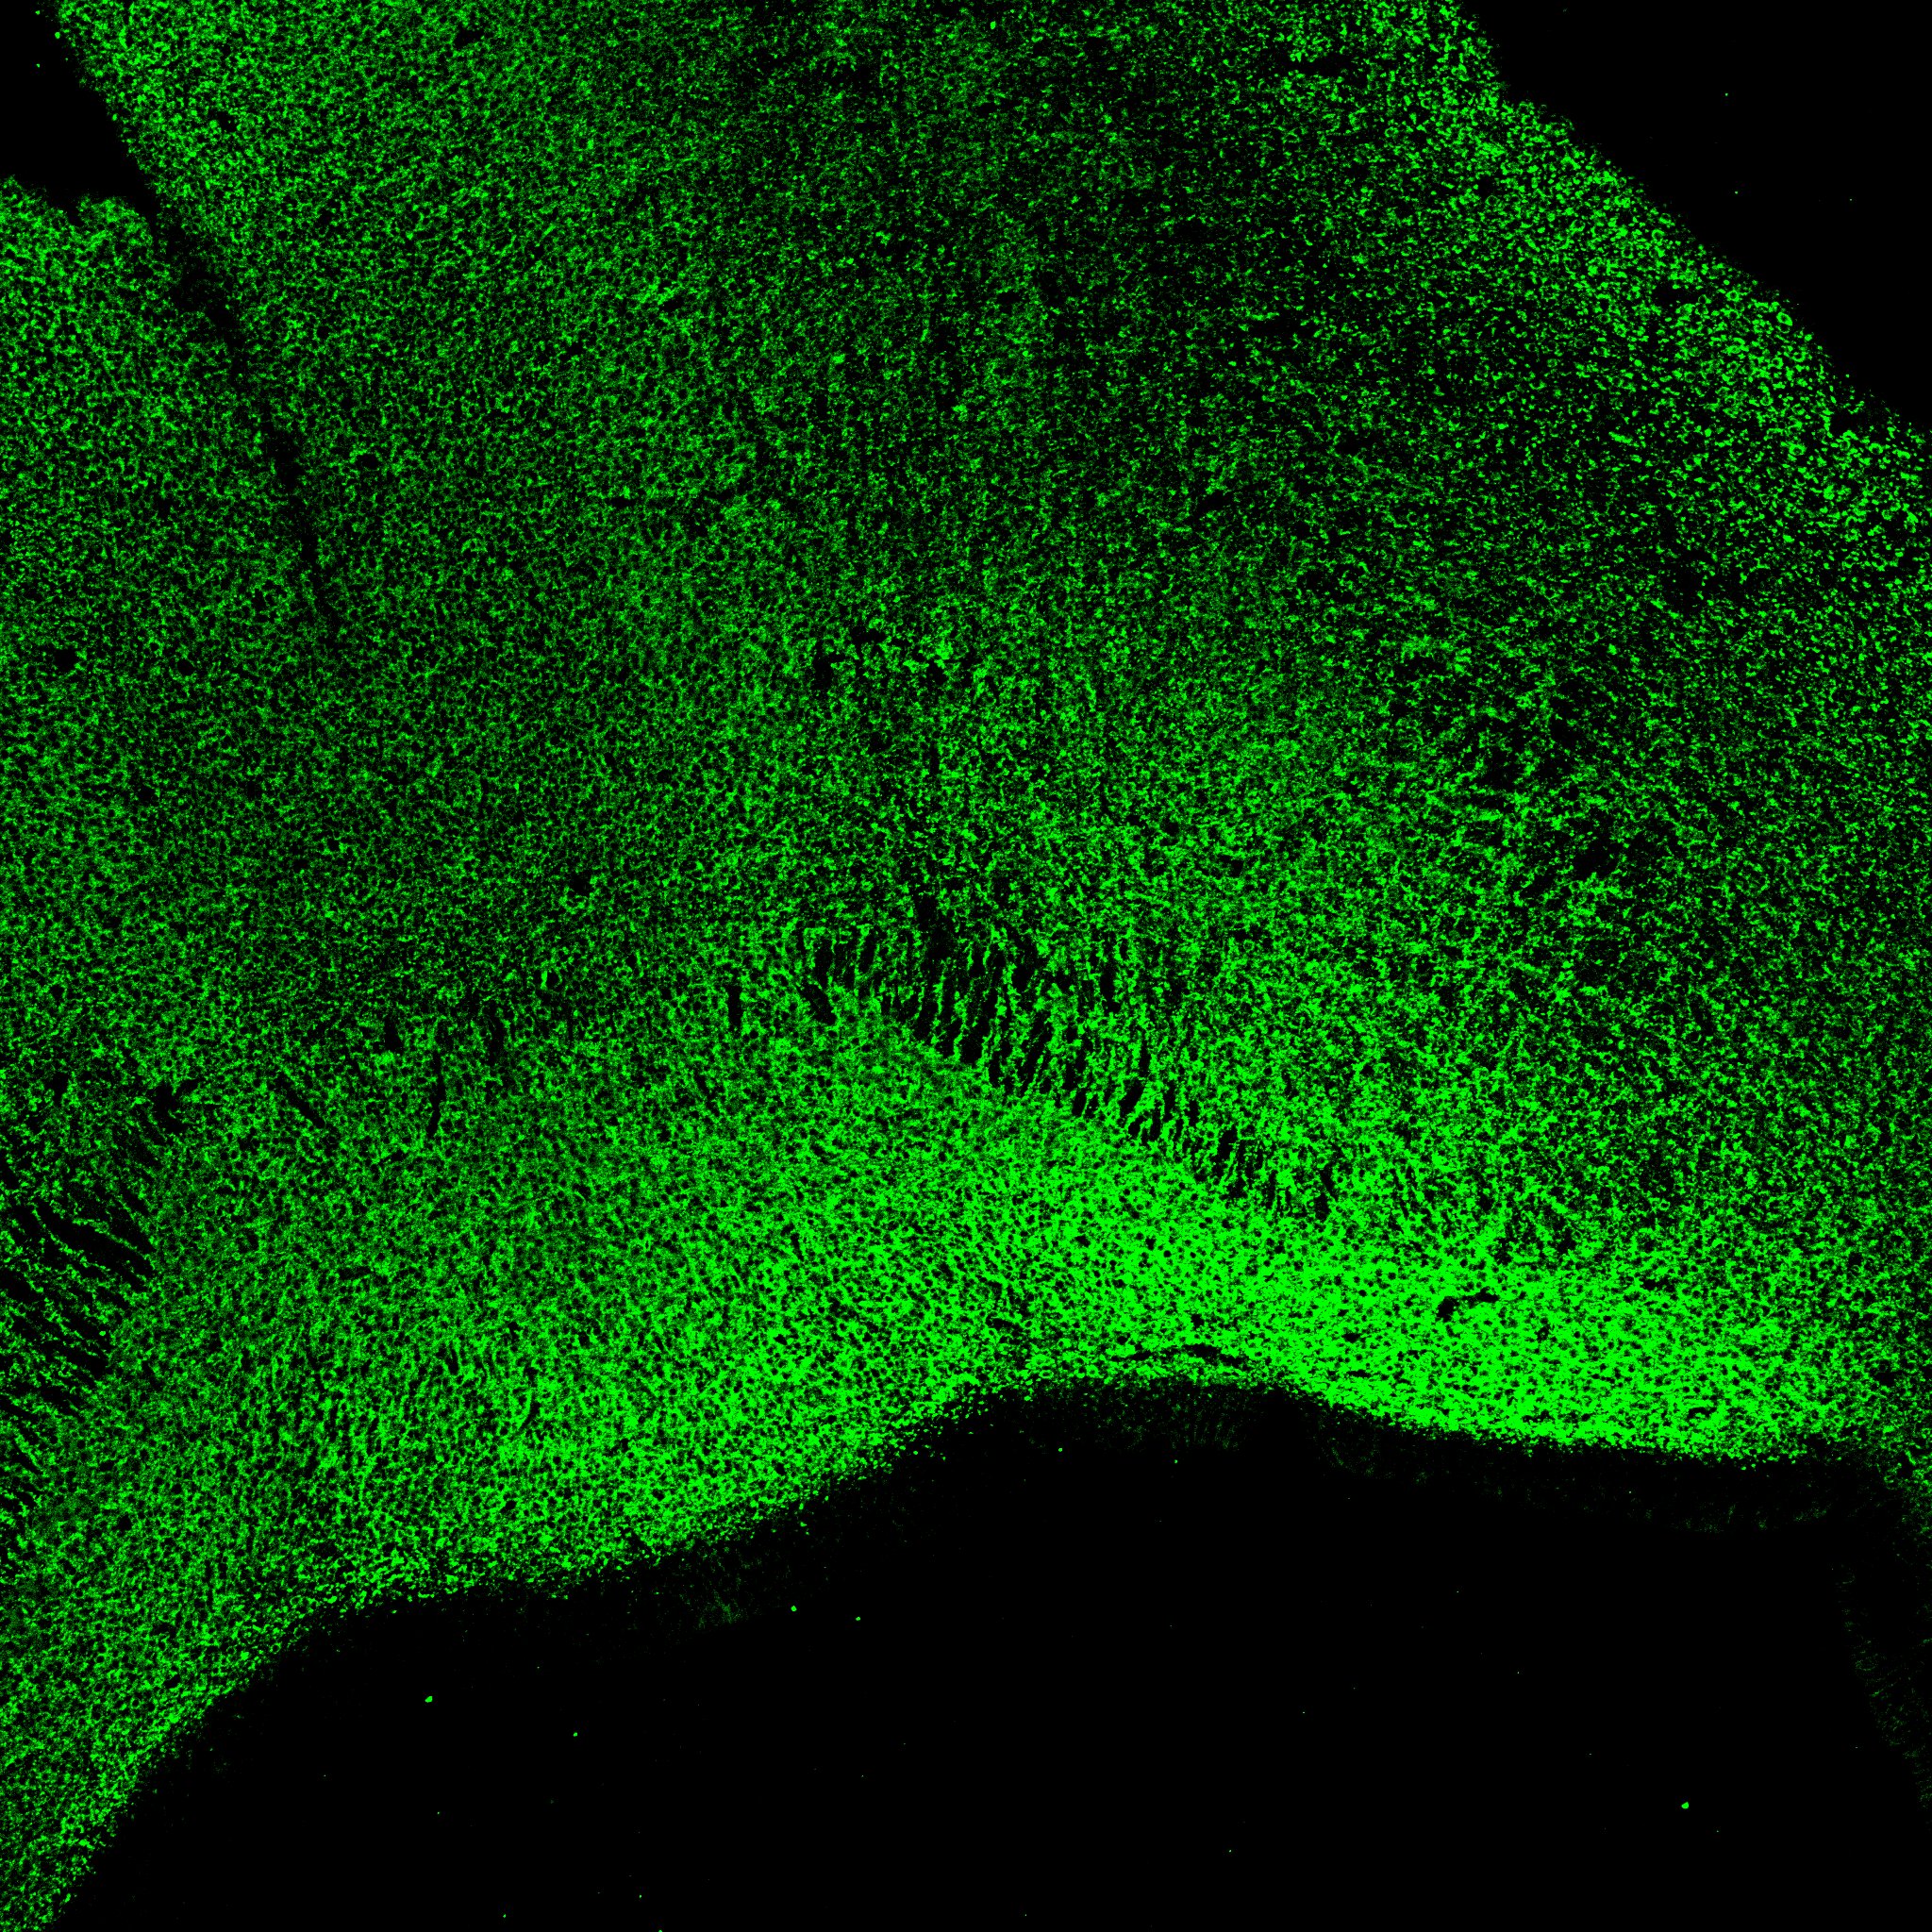

An anatomical analysis of the developing human midbrain from 6 post-conceptional weeks (PCW) to 22 PCW reveals increased tissue complexity, characterized by the emergence of dopaminergic nuclei, as highlighted by immunofluorescence analysis for tyrosine hydroxylase (TH).

6PCW

6PCW human midbrain